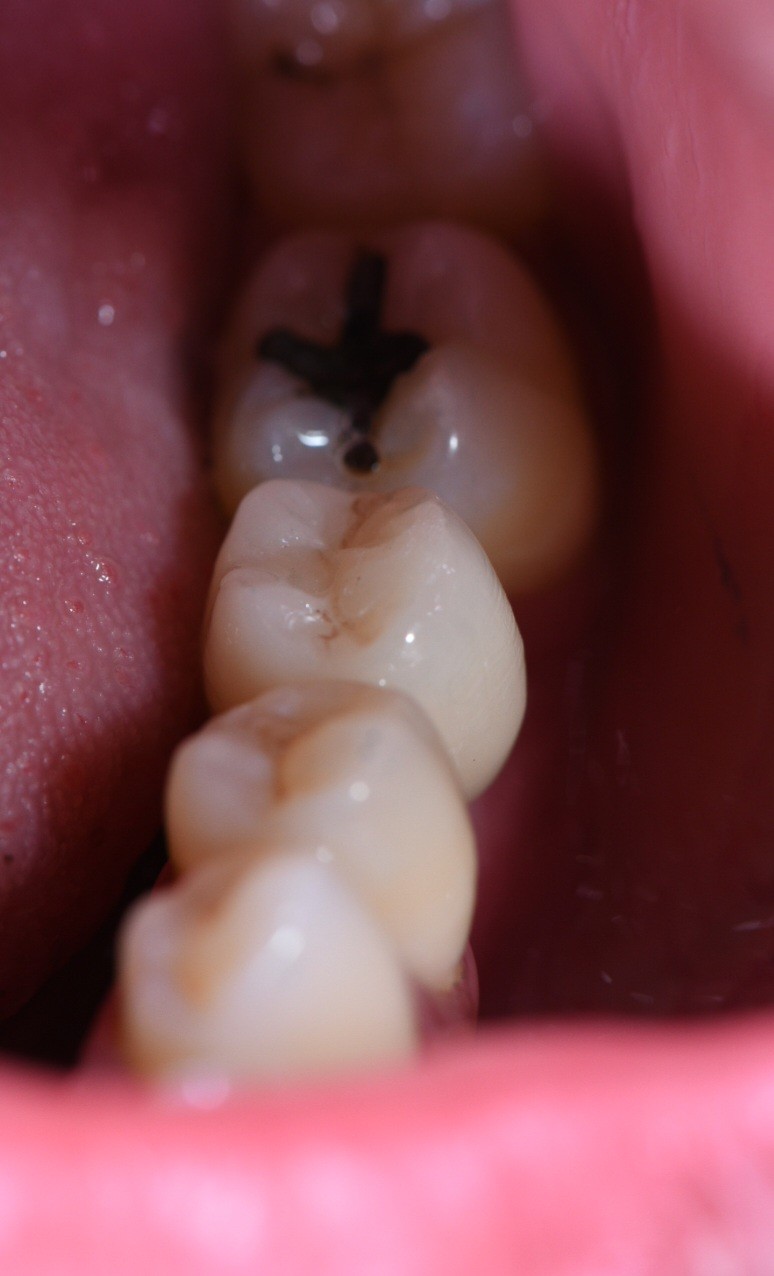

3 mois après cicatrisation , nous reprenons notre camera en main, et cette fois ci, nous allons prendre l’empreinte de notre « scanbody » qui est le transfert d’empreinte numérique (fig. 4) correspondant à notre implant (Megagen). C’est la que la magie opère… Fini les portes empreintes individuels, à perforer etc. On place le scanbody et on prends l’empreinte (haut , bas , occlusion). On peut même prendre le profil d’émergence sur un scan supplémentaire en quelques secondes.

L’empreinte est envoyée sur la plateforme et la conception est réalisée (fig. 5). Idem à ce stade vous pourrez valider la forme, le profil d’émergence etc.